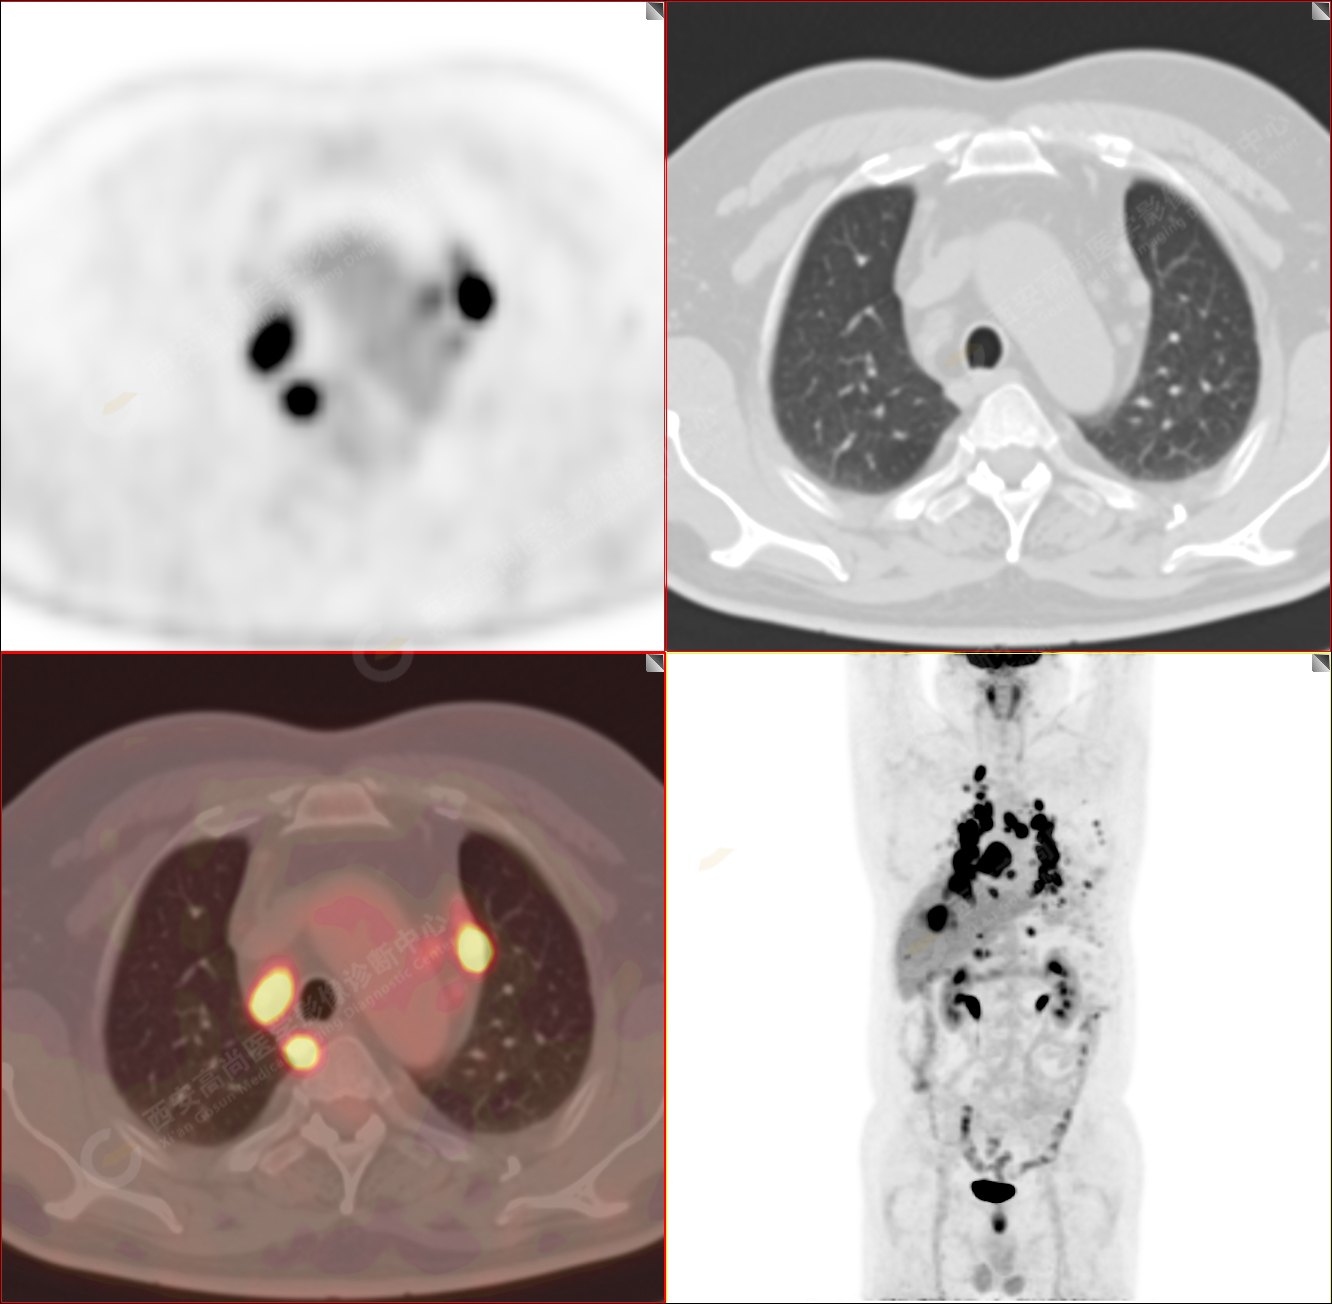

男性,53歲,頭暈半月入院,CT發(fā)現(xiàn)肺內(nèi)腫塊,雙肺多發(fā)大小不等實(shí)性及粟粒樣結(jié)節(jié),雙肺門(mén)及縱隔多發(fā)腫大淋巴結(jié)。病程中無(wú)發(fā)熱、胸悶氣及胸部不適。既往:左側(cè)肋骨外傷史。

PET/CT圖像